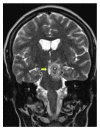

We report a case of a Somali refugee who presented in the second trimester of her first pregnancy with a four-week history of gradual right-sided sensomotoric hemisyndrome including facial palsy and left-sided paresis of the oculomotorius nerve causing drooping of the left eyelid and double vision. Cranial magnetic resonance imaging revealed a solitary brainstem lesion. Upon detection of hilar lymphadenopathy on chest X-ray (CXR), the diagnosis of disseminated tuberculosis with involvement of the central nervous system was confirmed by PCR and treatment induced with rifampicin, isoniazid, pyrazinamide, and ethambutol. The patient had a steady neurological improvement and a favorable pregnancy outcome.